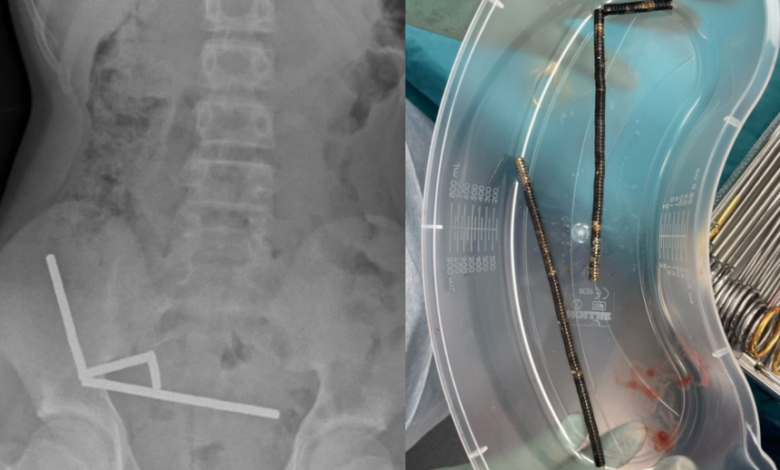

- X-rays showed a dangerous configuration of magnets in his abdomen, forming four chains.

- Doctors noted that the magnets were creating pressure necrosis in sections of his bowel and large intestine.

Due to the severity of his condition, an exploratory surgery was performed, during which surgeons successfully removed the magnets and addressed the damaged areas of his bowel. He spent eight days in the hospital recovering before being discharged.